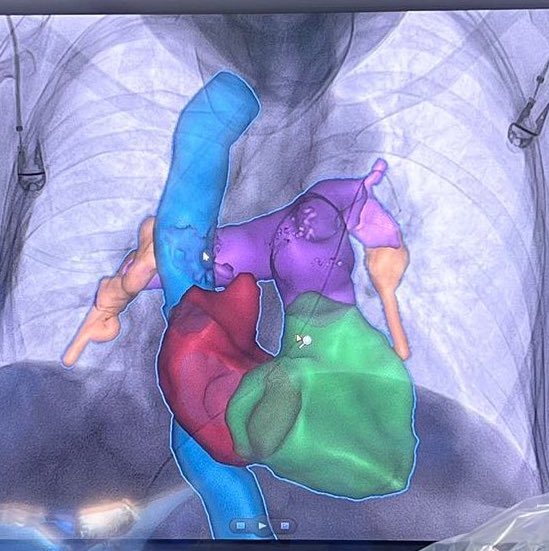

TEP, sistemas de trombectomia, equipos PERT entrenados, Guias de navegación endovascular. Resultados inmediatos. 🇨🇱 Temuco 💪 @HHHATEMUCO @RadiologiaChile @SIDISoc @colmedchile @DrCOlivares @InariMedical @teptips @rduranmendez

Tromboembolismo de arteria pulmonar o TEP. 3era causa de muerte cardiovascular. Araucania con terapia de 1er mundo. Guias de manejo actualizadas. Equipos PERT. Caso de la semana pasada 👌 Mejorando la salud de nuestra población con lo mejor que tiene la medicina, orgulloso

Caso trombectomía aspirativa en #TEP en ⁦@HHHATEMUCO#PE #FLAME #Irad@SIDISoc⁩ ⁦⁦@RadiologiaChile⁩ ⁦@sochimioficial⁩ ⁦@sochimu⁩ ⁦@Sochicaroficial⁩ ⁦⁦@SOCHIVAS_Chile⁩ ⁦@InariMedical#Flowtriever